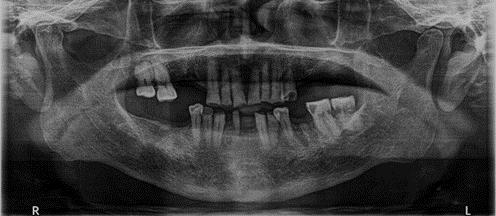

En la radiografía panorámica (Figura 3) se observan las raíces cortas de los incisivos centrales y del O.D. 22, además de los terceros molares superiores e inferiores en formación.

Figura 3. Radiografía Panorámica inicio.